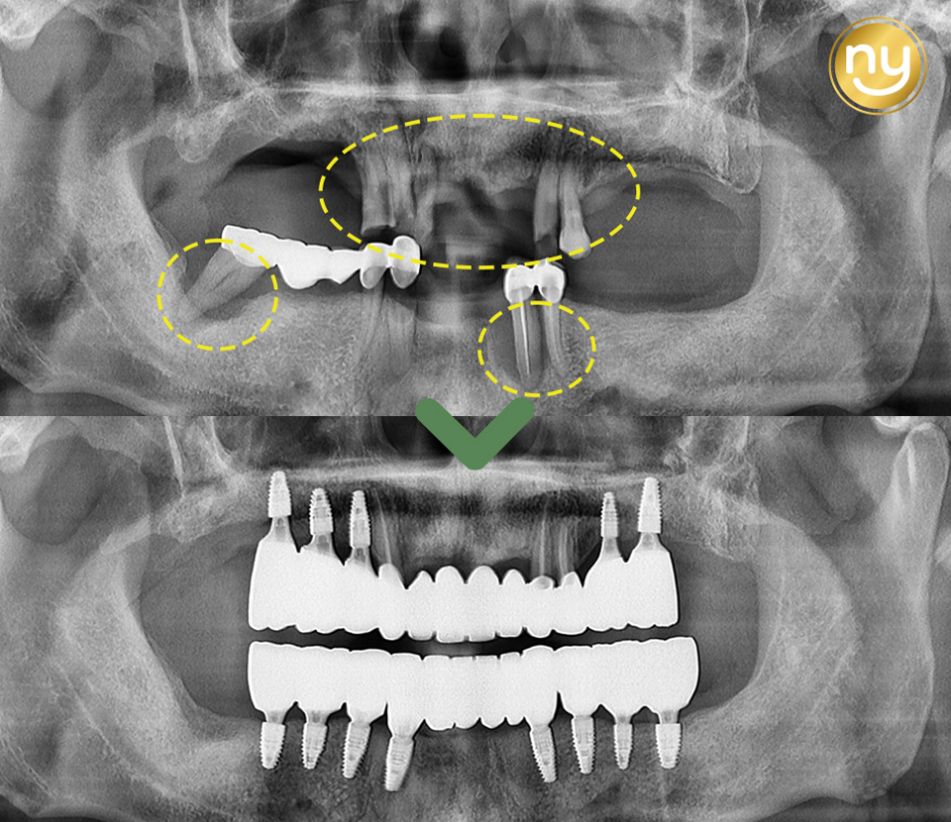

처음 본원에 내원하셔서 찍은 파노라마 사진입니다.

전체적으로 잇몸뼈의 소실이 심하고

하악의 브릿지와 크라운을 수복한 치아들도

염증이 발생되어 있는 것을 보실 수 있는데요.

염증과 치주 질환으로 인해 치아 흔들림이 심해 상악 송곳니 2개와

작은 어금니 1개를 제외하고는 살릴 수 있는 치아가 없어서

나머지 치아들은 발치를 진행하기로 했습니다.

상악 앞니 들은 살려서 사용이 가능한 3개의 치아를 이용하여

브릿지를 제작하여 전치부의 기능을 회복하였는데요.

상악 구치부의 경우 오른쪽 3개, 왼쪽 2개를 식립하여

어금니의 역할을 수행할 수 있도록 제작해드렸는데요.

상악의 경우 잇몸뼈가 많이 소실되어 있는 상태라

길이가 짧은 임플란트를 사용하여 식립하였고

별도의 뼈이식 없이 임플란트 식립을 진행하였습니다.

하악에는 전치부 2개, 구치부 각 오른쪽 4개,

왼쪽 3개의 임플란트 식립으로 총 12개 치아의 기능을 회복하였습니다.

하악 오른쪽 뒤 큰 어금니와 왼쪽 송곳니 쪽에는 염증이 심했던 상태라

임플란트의 식립이 어려워, 큰 어금니 1개를 제외하고

위아래 모두 12개씩 총 24개의 치아 기능을 회복하였습니다.

전체적인 기간은 1년이 걸렸으며,

임플란트 식립 전 본원에서 당 조절을 항상 강조해 드렸고

조절을 잘 해주셔서 임플란트가 성공적으로 마무리되었습니다.